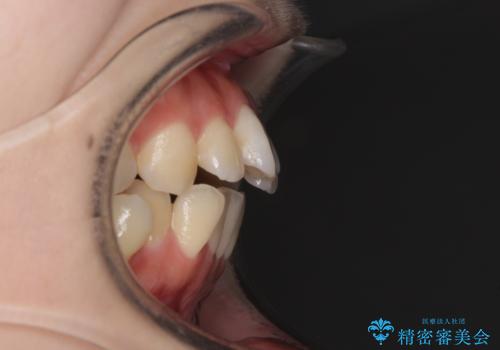

目立たない裏側矯正で突出感を改善 ハーフリンガル矯正

- ハーフリンガル

- 口元の突出感を気にして来院された患者様です。

上下左右の第一小臼歯4本を抜歯して口元を下げる治療計画としました。

裏側矯正特有の抜歯スペースに前後の歯が倒れ込む状態が長く続き、改善に長期間を要しました。